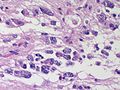

Microscopic

Features:

- Large cell lymphoma.

- Size = 2x diameter normal lymphocyte.

- Nucleolus - common.

- Perivascular clustering.

Images